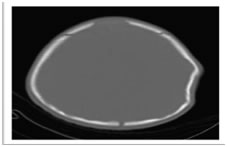

Figure 4: Axial NECT scan with bone window of a 5- month old baby was presented after falling down from bed shows ping pong fracturein left parietal bone.